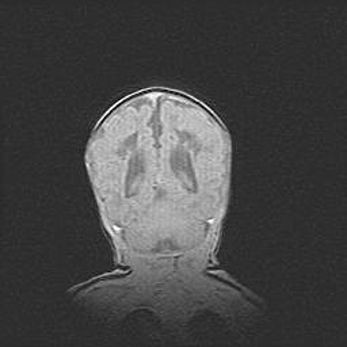

Аномалия Денди-Уокера. Признаки гипоплазии мозолистого тела.

Возраст: 5 месяцев 3 дня

Вес: 5550 г

Пол: мужской

Окружность головы: 39 см

Срок гестации: 40 недель

Аномалия Денди-Уокера – это порок развития головного мозга, для которого характерна триада симптомов: гипотрофия или аплазия червя мозжечка и/или полушарий мозжечка, расширение четвёртого желудочка с формированием ликворной кисты задней черепной ямки, гипертензионная гидроцефалия различной степени.

Гипоплазия мозолистого тела относится к дефектам внутриутробного этапа развития мозговой ткани, возникающим в процессе закладки структур головного мозга, что происходит на начальных этапах развития эмбриона.